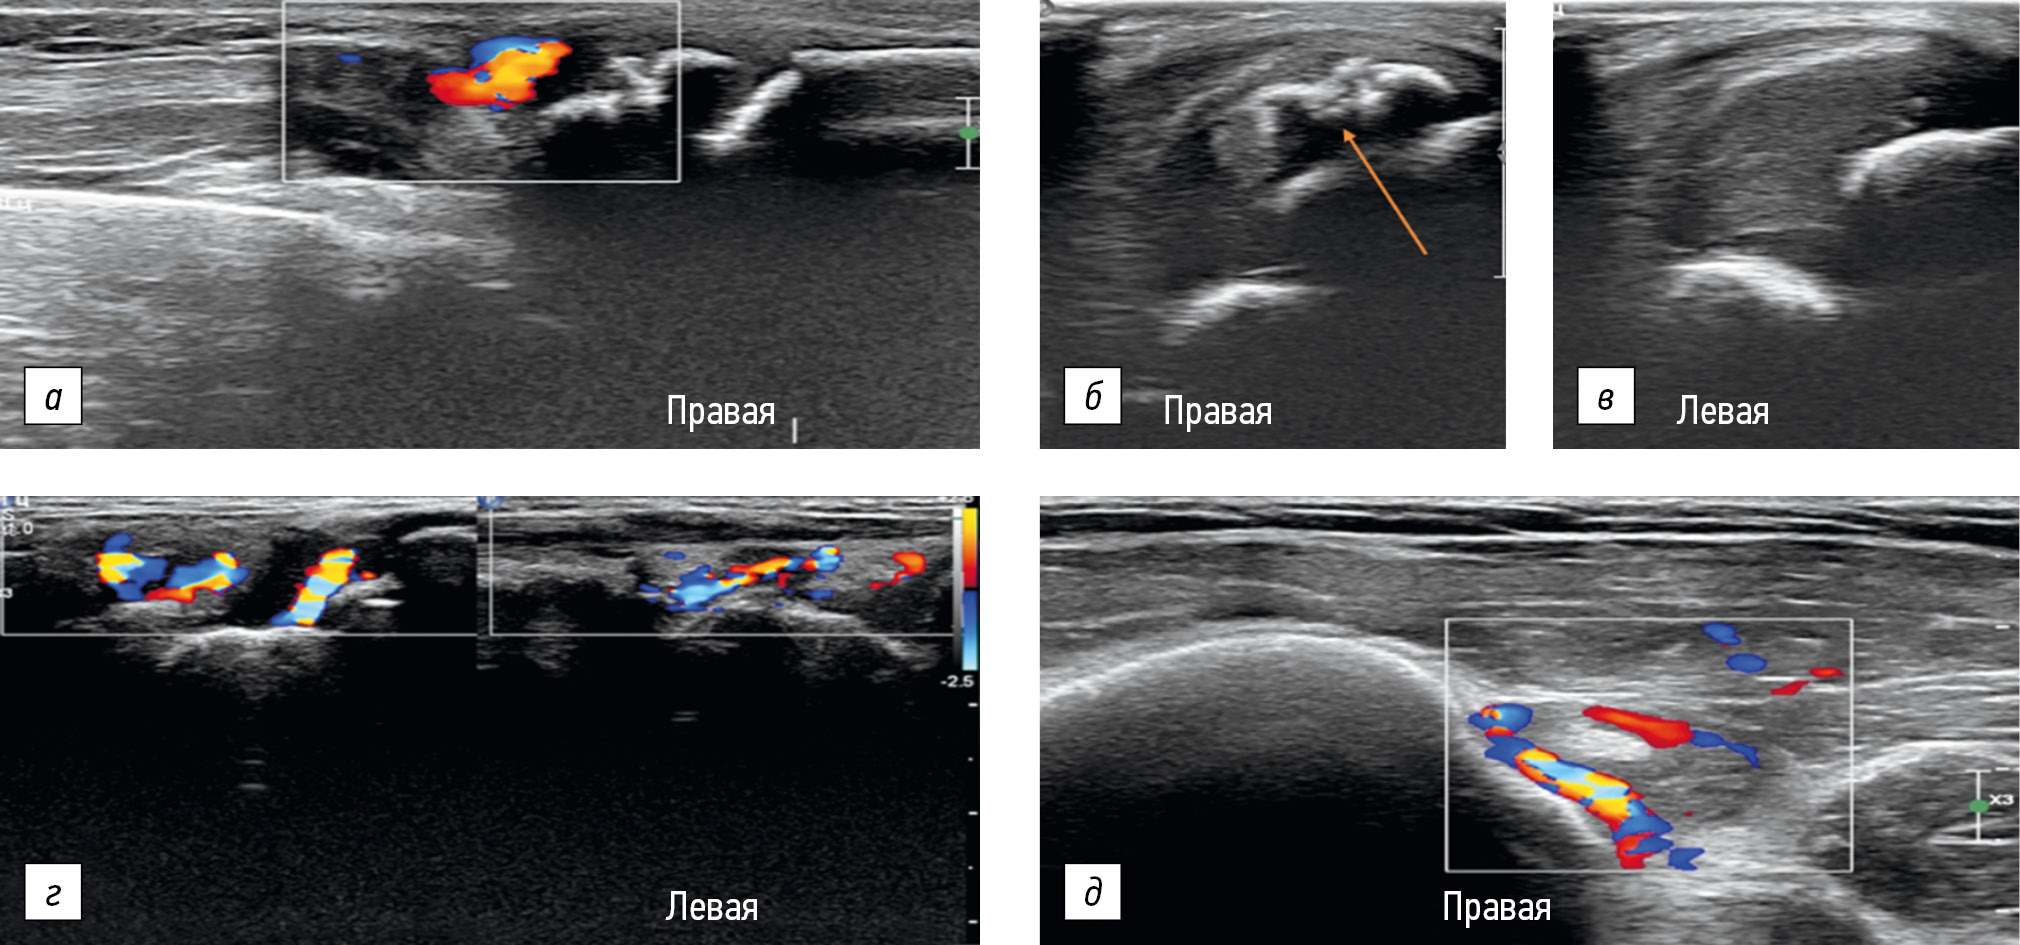

All layers of enthesis must be visualized. The fibers of the tendon part of the enthesis in the zone of transition to its cartilaginous part change direction, which gives the effect of anisotropy (appearance of pseudo-reduced echogenic zones). The assessment of this effect is diagnostically significant in the ultrasound examination of the tendon part of the enthesis. The presence of anisotropy indicates the preservation of the enthesis zone. In the pathological process, the tendon–cartilage–bone zonality is disturbed, and this effect is not recorded. At the initial stages of enthesopathy development, the cartilaginous component may not be involved in the process, and ultrasound will register changes in the tendon, primarily as increased blood flow in the color Doppler mapping mode (Fig. 3). In the future, changes will become visible in the B-mode (Fig. 4). When tendons, cartilage, and bones are involved, their echogenicity and echostructure are altered [20].

Fig. 3. Enthesopathy of the tendon of the triceps brachii muscle and increased vascular pattern in the color Doppler mapping mode (a); cartilage changes in the enthesis site (joint in the Fig. a with enlargement) in the gray-scale mode, unclear contours with sites of bone tissue remodeling (indicated by an arrow) (b); ultrasound presentation of the unchanged elbow joint (c); and enthesitis with severe hypervascularization of the tendon of the triceps brachii (d, e)